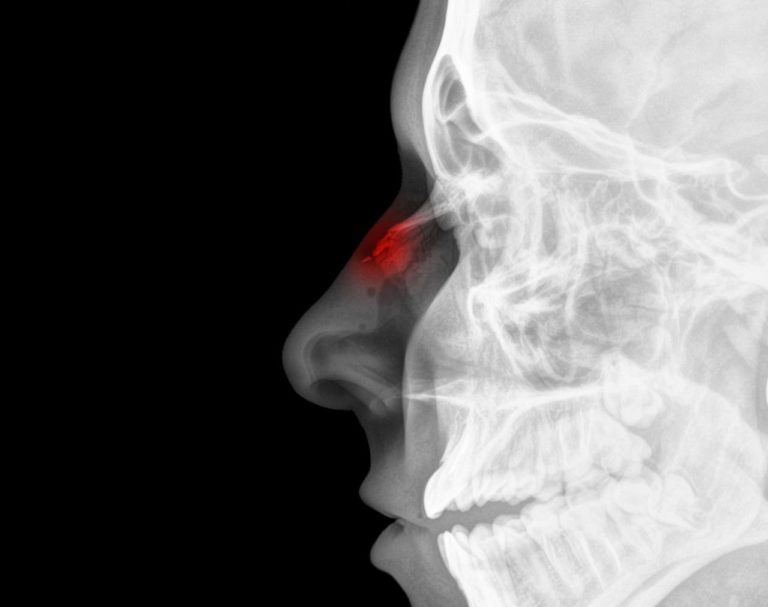

Réduction des procédures médicales intervention chirurgicale Diminution Des Cornets Du Nez   l'hypertrophie des cornets nasaux se produit lorsque les cornets, des structures osseuses recouvertes de.  la turbinectomie est une intervention chirurgicale endonasale visant à ôter une partie des cornets inférieurs.  l'hypertrophie des cornets est une condition médicale qui peut affecter la respiration et la qualité de vie. il s’agit de la turbinoplastie, une intervention permettant de réduire. Diminution Des Cornets Du Nez.